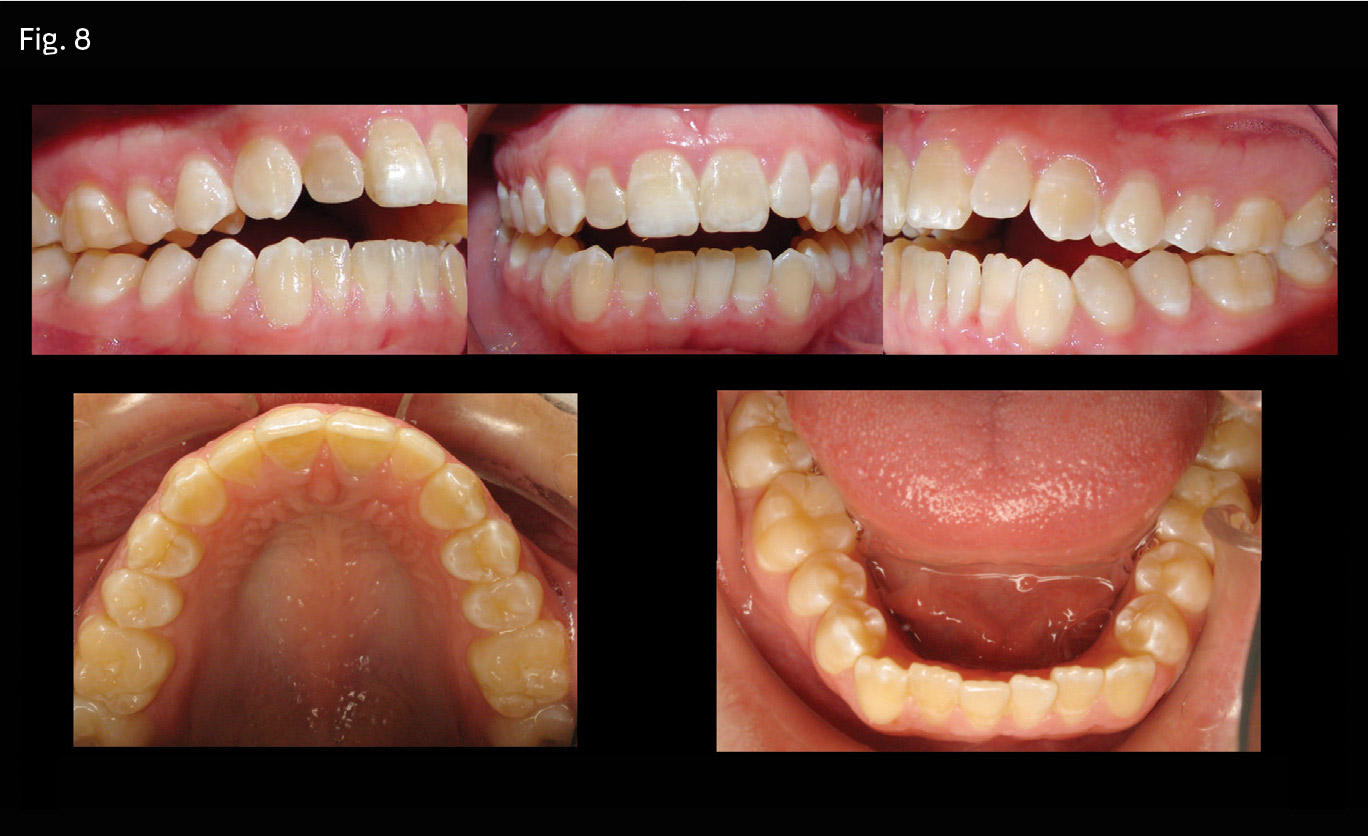

Patient (Figs. 7 and 8) presented with a chief complaint of not being able to function adequately due to an open-bite malocclusion. The patient reported being prescribed Ortho-Novum birth control pills at age 14 to alleviate menstrual cramping. She reported a progressive worsening of her open bite that was first noticeable at age 16.

Anteroposterior: Class II skeletal/dental malocclusion. Loss of mandibular condyle anatomy secondary to birth control pills. Class II molar half-step. Excess overjet. Convex profile.

Vertical: Open bite of 6mm measured at the upper-left lateral incisor. Dolichofacial facial pattern.

Transverse: Within normal limits.

Perimeter: Moderate upper and lower crowding.